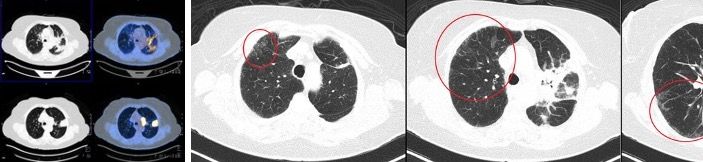

In an asymptomatic 77-year-old woman, former 55 pack-years smoker, a routine X-ray showed a 45-mm superior left lobe lesion (Figure 1). A chest CT scan confirmed a 36-mm superior left lobe lesion and an aortic-pulmonary lymph node enlargement measuring 42 mm, suspicious for neoplasia (Figure 2). A PET-CT scan showed an elevated uptake in the primary lesion, in the aortic-pulmonary lymph node, and in the left hilar lymph node with a standardized uptake value – 40 and 4.3, respectively (Figure 3).

After multidisciplinary team consultation, the patient received radiotherapy (Figure 4) with concurrent weekly paclitaxel and carboplatin. The treatment was well tolerated, and the patient had no toxicity. A CT scan after therapy showed a good response (Figure 5). After chemo-radiotherapy treatment, the patient started durvalumab as consolidation therapy.

Three months after starting durvalumab, the patient developed a dry cough with no other symptoms. Physical examination was normal and oxygen saturation was 96%. The patient denied contact with coronavirus disease 2019 (COVID-19) positive patients and was practicing all measures of COVID-19 protection. A new PET-CT showed an excellent tumor response, with appearance of some ground-glass opacity in the lungs (Figure 6). A polymerase chain reaction (PCR) naso- and oropharyngeal test to detect severe acute respiratory syndrome (SARS) coronavirus 2 (SARS-CoV-2) was negative, as was the full respiratory viral panel. A subsequent durvalumab dose was put on hold to better define the diagnosis. After 48 hours, the patient repeated the SARS-CoV-2 test; the results were again negative. Due to the COVID-19 pandemic and her very good clinical status, the patient did not receive corticosteroids at this time and was instead monitored every 48 hours with telemedicine. The cough disappeared after 1 week and a new COVID-19 test was negative. Durvalumab was reinitiated 2 weeks later and the patient is still receiving the medication with no new symptoms, with a very good tolerance. After 3 months a new PET-CT (Figure 7) showed an almost complete resolution of the ground-glass opacity, and the patient maintains an excellent response.

Another challenge is that imaging findings from both causes of pneumonitis can be indistinguishable. The most common presentation in COVID-19 patients is the pattern of ground-glass opacities seen on a CT scan of the chest, which is a possible characteristic of IMT-related pneumonitis.6,11,16 Therefore, statement A is correct.

Figure 3. PET-CT with pulmonary and lymph node involvement.

Figure 6. PET-CT with an excellent tumor response and appearance of ground-glass opacity.